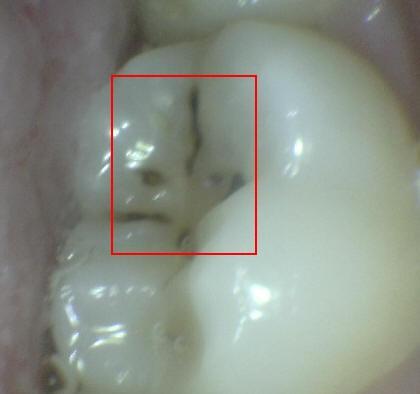

2. PERDIDA DE LA INTEGRIDAD DE LA SUPERFICIE

1. HALLAZGO: macha café con presencia de cavidad

1. CRITERIO DE DIAGNOSTICO: despues de secar por 5 sg, existe una pérdida de integridad superficial sin exposición de dentina

1. DIAGNOSTICO

1. ICDAS 3

2. TRATAMIENTO

1. operatoria

2. ACTIVIDAD

1. activa/detenida